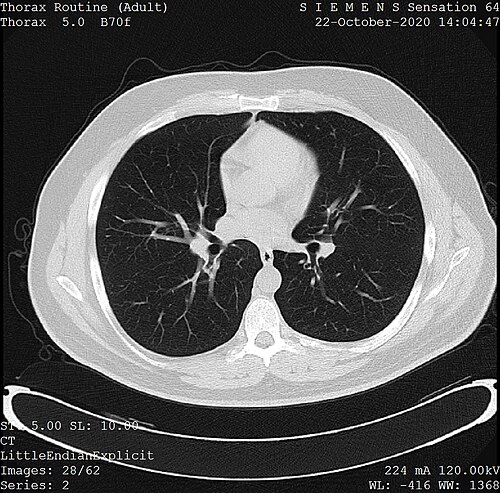

Diagnostic Radiology is a medical specialty focused on interpreting X-ray-based and cross-sectional imaging studies to assist clinical decision-making in hospitals such as Mayo Clinic, Johns Hopkins Hospital, and Massachusetts General Hospital. Practitioners collaborate with specialists from institutions like Cleveland Clinic, Karolinska Institutet, and Imperial College Healthcare NHS Trust and contribute to multidisciplinary teams including members from American College of Radiology, Royal College of Radiologists, and European Society of Radiology. The specialty relies on technologies developed by companies and institutions such as GE Healthcare, Siemens Healthineers, and Philips Healthcare and is regulated in many countries by bodies like the General Medical Council, Medical Council of Canada, and Australian Health Practitioner Regulation Agency.

Modalities include projection radiography pioneered in settings such as Hôpital Necker–Enfants Malades, cross-sectional techniques like computed tomography developed at Atkinson Morley Hospital and University of Pennsylvania, and magnetic resonance imaging innovations linked to University of Nottingham and Massachusetts Institute of Technology. Ultrasound applications evolved with research from Karolinska Institutet and clinical programs at Guy's and St Thomas' NHS Foundation Trust, while nuclear medicine procedures relate to advances at Johns Hopkins University and Mayo Clinic. Interventional techniques emerged from programs at Stanford University Medical Center and UCLA Medical Center, and newer methods include hybrid PET/CT and PET/MRI promoted by collaborations involving Harvard Medical School, University of Cambridge, and University of Toronto.

Clinical practice is organized into sub-specialties practiced at centers like Cleveland Clinic and Mount Sinai Health System: thoracic imaging practiced in programs affiliated with Royal Brompton Hospital and MD Anderson Cancer Center, neuroradiology carried out at Mayo Clinic and Massachusetts General Hospital, musculoskeletal imaging at Hospital for Special Surgery and Toronto General Hospital, and pediatric radiology at Great Ormond Street Hospital and Children's Hospital of Philadelphia. Emergency radiology services operate in concert with trauma centers such as Royal London Hospital and R Adams Cowley Shock Trauma Center, while breast imaging programs are established at Memorial Sloan Kettering Cancer Center and Christie's NHS Foundation Trust. Multidisciplinary tumor boards and collaborations involve institutions like National Cancer Institute, European Organisation for Research and Treatment of Cancer, and World Health Organization.